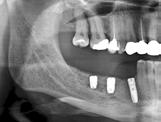

grænsning af canalis mandibulae. I præmolarregionen er det også relevant at identificere foramen mentale. Til det formål anvendes røntgenoptagelser, som desuden vil kunne afsløre patologiske tilstande, der skal behandles før implantatindsættelsen. Periapikale røntgenoptagelser har typisk en forholdsvis høj billedopløsning og vil i teorien være ideelle til at visualisere fx canalis mandibulae. Ulempen er den begrænsede størrelse af billedfeltet, hvorfor det kan være vanskeligt at få relevante anatomiske strukturer gengivet på billedet i hele deres udstrækning. Panoramabilleder dækker et større område af kæben og er, på trods af en lidt ringere billedopløsning i forhold til periapikale optagelser, derfor ofte oplagte ved implantatplanlægningen, specielt hvis det drejer sig om større behandlinger med indsættelse af flere implantater. Panoramabilledet giver et godt overblik over hele tandsættet og kæberne, hvormed patologiske tilstande, som skal behandles inden eventuel implantatbehandling, kan identificeres. I visse tilfælde kan det være relevant at anvende segmenterede optagelser, så man fx ved planlægning posteriort i mandiblen kan fravælge bestråling af øvrige områder og hermed reducerer stråledosis.

Da et implantat ideelt set skal være omgivet af 1-2 mm knogle langs hele implantatoverfladen, vil der i tilfælde af en smal knoglekam være risiko for, at implantatet bliver placeret dybt, hvor implantatets skulder således forsænkes i forhold til den mest marginale begrænsning af processus alveolaris. Dette kan bl.a. medføre en uhensigtsmæssig krone-implantat-ratio. Klinisk og radiologisk vurdering af knoglens bredde er derfor også nødvendig for at kunne bestemme den mest optimale implantatlængde, inklusive om der er behov for horisontal knogleopbygning enten før eller i forbindelse med implantatindsættelsen (Fig. 3). Dette er naturligvis ikke muligt med todimensionale (2-d) røntgenoptagelser, og en klinisk vurdering af breddeforholdene med palpation og evt. ”ridge mapping” (9) eller ved hjælp af tredimensionale (3-d) røntgenoptagelser vil derfor ofte være nødvendig. Det skal her nævnes, at en 3-d-optagelse også kan afklare, hvordan canalis mandibulae er orienteret i det facioorale plan, hvilket ligeledes kan influere på behandlingsplanlægningen.

Undersøgelser har vist, at canalis mandibulae er mere synlig på CBCT-snitbilleder end på panoramabilleder (13,14). En undersøgelse fandt, at canalis mandibulae og foramen mentale kunne identificeres på alle de undersøgte CBCT-billeder af yngre personer og med god visibilitet af canalis mandibulae på 51 % og foramen mentale på 98,5 % af billederne (13). På panoramabillederne kunne canalis mandibulae udelukkende identificeres på 93 % af billederne (12 % med god visibilitet) og foramen mentale på 45 % af billederne (0 % med god visibilitet). En anden undersøgelse viste endvidere, at canalis mandibulae på både CBCT- og panoramabilleder er mest synlig svarende til den distale del af kanalen, og at synligheden afhænger af kanalens forløb, hvor det var sværest at se kanaler med et lineært (lige linje, modsat et elliptisk, skeformet eller knækket) kurveforløb (14). Af og til kan det være svært at identificere canalis mandibulae i et specifikt område, hvor implantatindsættelsen er planlagt, og man kan også forveksle kanalen med et marvrum i knoglen på rekonstruerede CBCT-

tværsnitsbilleder. Et tip til, hvorledes man kan lette identifikationen, er i det koronale plan først at identificere foramen mandibulae posteriort. Herefter ”bladrer” man gennem de koronale tværsnit posteriort fra i anterior retning mod implantatstedet og holder øje med canalis mandibulae hele vejen. Alternativt kan man lokalisere foramen mentale og bevæge sig i posterior retning (Fig. 4). Ved hjælp af scanningssoftwaren kan canalis mandibulae oftest indtegnes, således at kanalen kan følges i alle snitplanerne (Fig. 4).

Udover en god visualisering af de nævnte strukturer er det naturligvis også afgørende, at måling af dimensioner og afstande er pålidelig på røntgenbillederne. Det er velkendt, at der for 2-d-optagelser ses projektionsforstørrelse (15,16). Det er vist, at en forstørrelse horisontalt og vertikalt på 5-10 % gennemsnitligt skal påregnes på periapikale optagelser med parallelteknik (17). Forstørrelsen varierer dog meget og afhænger primært af afstanden mellem objektet og receptoren. For panoramaapparatur anfører fabrikanterne typisk en forstørrelsesgrad på 20-25 % i gennemsnit, men ovennævnte undersøgelse viste, at forstørrelsen på panoramaoptagelser varierer meget fra optagelse til optagelse med forskelligheder i de to plan og i forskellige regioner (17). I den forbindelse skal det nævnes, at positioneringen af patienten i røntgenapparatet har stor betydning for projektionsforstørrelsen. Patienten skal placeres korrekt i apparatet i forhold til midterplanet (lodret), Frankfurt-horisontalplanet samt hjørnetandslyslinjen, således at kæberne ligger inden for skarphedszonen. Det er således afgørende, at der kompenseres for forstørrelsen ved målinger på billederne. En metode til dette er kuglekalibrering, hvor man ved placering af en metalkugle med kendte dimensioner (typisk Ø 5 mm) i det aktuelle område efterfølgende kan beregne den reelle forstørrelse (17). Da forstørrelsen, som sagt, varierer afhængigt af region (maksil/mandibel, anteriort/posteriort), skal kuglen placeres så tæt som muligt på det sted, hvor implantatet planlægges indsat (Fig. 5). Det betyder, at der skal anvendes en kugle for hvert implantatsted. Korrekt placering

På CBCT-optagelser ses der i praksis ingen projektionsforstørrelse, og målingerne foretaget ved hjælp af scanningssoftwarens måleværktøj anses for målfaste. I mange af softwareprogrammerne, som findes på markedet, kan man gøre brug af såkaldte implantat-attrapper i forskellige størrelser og design og derved foretage en virtuel implantatindsættelse før operationen (Fig. 6).

fakter, fx forårsaget af patientbevægelse under optagelsen (19). Det kan derfor anbefales at arbejde med en sikkerhedsmargen på ca. 2 mm til ”kritiske” anatomiske strukturer ved implantatplanlægning på CBCT-billeder. I en undersøgelse blev målinger foretaget på basis af henholdsvis CBCT og panoramabilleder sammenlignet (20). Undersøgelsen viste, at nøjagtigheden af vertikale, lineære mål i forbindelse med implantatplanlægning var tilstrækkeligt for begge modaliteter. En anden undersøgelse konkluderede, at de tilgængelige vertikale knogledimensioner for implantater posteriort i underkæben blev undervurderet på panoramabilleder i forhold til på CBCT-billeder, og sidstnævnte kunne derfor anbefales ved bestemmelse af passende implantatlængde og diameter i denne region (20). Det kan således ligeledes anbefales at anvende en sikkerhedsmargen på ca. 2 mm ved vurdering af afstanden til canalis mandibulae på panoramabilleder (21).

Omhyggelig planlægning før implantatbehandling er afgørende for at kunne træffe det rigtige valg i forhold til behandlingsmetode samt sikre et forudsigeligt behandlingsresultat med en god langtidsprognose og mindst mulig risiko for komplikationer. Dimensionerne, pladsforholdene i mandiblen og afstanden fra toppen af processus alveolaris til den øvre begrænsning af canalis mandibulae er de væsentlige parametre, som har betydning for valg af behandling. I dette temanummer vil tre behandlingsteknikker, som kan anvendes i den atrofiske posteriore mandibel, blive nærmere gennemgået involverende transposition eller lateralisering af NAI (ved en højde af processus alveolaris på ca. 0-4 mm), sandwich-osteotomi (højde på ca. 4-8 mm) og indsættelse af korte implantater (højde på > ca. 8 mm) (Fig. 7). De undersøgelsesmetoder, man vælger i forbindelse med behandlingsplanlægningen, skal gerne være til gavn for patienten og med færrest mulige ulemper. Man skal derfor arbejde

I den atrofiske posteriore mandibel, som er karakteriseret ved en væsentlig reduktion af processus alveolaris’ dimensioner og formindsket plads til implantater, skønnes det, at CBCT ofte er indiceret ved behandlingsplanlægningen, da dette værktøj bedst kan visualisere de relevante anatomiske strukturer og give pålidelige mål, samtidig med at knoglens bredde kan bestemmes.

SAMMENFATNING

Behandlingsplanlægning før implantatindsættelse i den atrofiske posteriore mandibel indebærer nøje vurdering af knoglebredden og -højden, inklusive afstanden til canalis mandibulae. Dimensionerne af processus alveolaris og pladsforholdene kan bl.a. have betydning for valget af behandlingsmetode. Et hensigtsmæssigt valg af undersøgelsesmetode, herunder røntgenoptagelser, er afgørende for ikke at udsætte patienten for unødig røntgenbestråling samt at minimere risikoen for neurosensoriske forstyrrelser som følge af nerveskade eller intraoperative blødninger. Det kan således konkluderes, at CBCT-scanning ofte er indiceret i forbindelse med implantatindsættelse i den atrofiske posteriore mandibel med henblik på vurdering af dimensionerne af processus alveolaris, inklusive visualisering af canalis mandibulae samt nærliggende anatomiske strukturer.